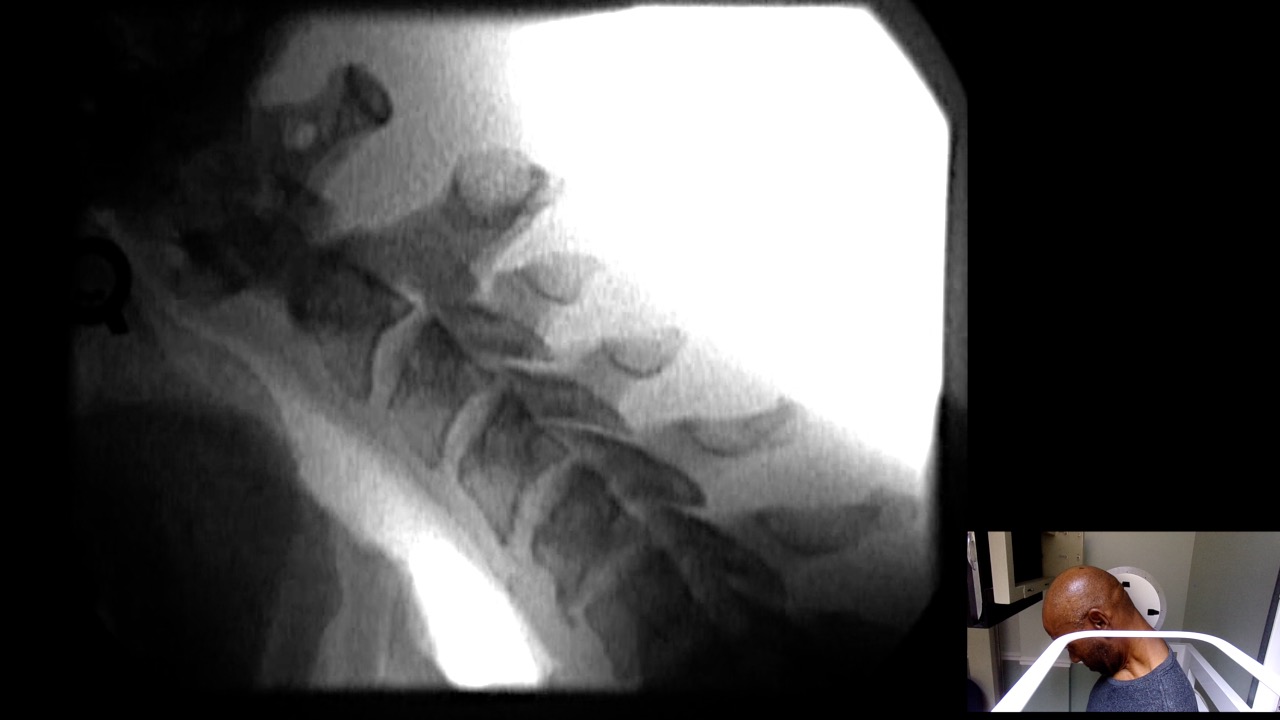

Image Name Image Type Image